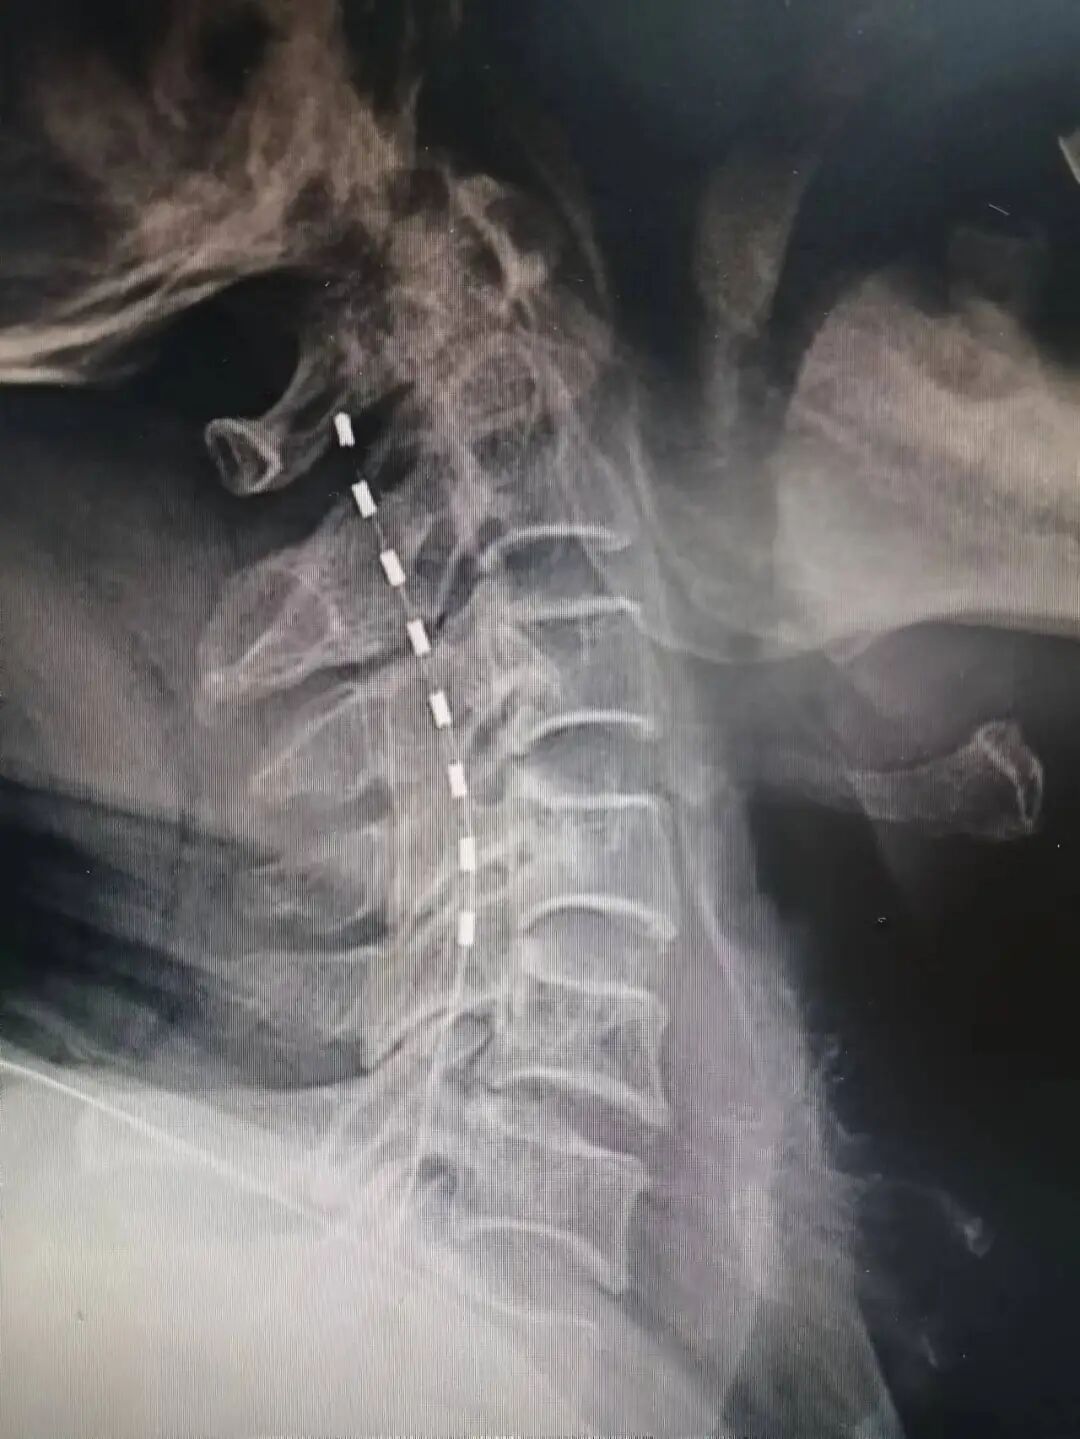

1.鞘内输注系统植入术

鞘内药物输注系统植入术是一种先进的微创介入镇痛技术。医生通过精准穿刺,将一根直径小于牙签的柔性导管置入对应脊神经节段,将镇痛药物直接、持续地输注至脊髓神经周围——即疼痛信号传导的关键区域,从而高效阻断痛觉传递,显著缓解顽固性疼痛。

该手术具有创伤小、靶向性强的优势,药物可直接作用于中枢神经系统,镇痛效果确切;用药剂量显著减少——达到同等镇痛效果时,仅需口服药量的1/300,从而降低药物相关副作用及治疗费用;患者可在医生指导下参与疼痛管理,实现安全、灵活的按需给药。

2020年1月,我院成功完成江门地区首例癌痛患者鞘内输注系统植入术;同年7月,又率先实施五邑地区首例带状疱疹后遗神经痛患者的鞘内输注系统植入术。

目前,我院疼痛科已成为广东省开展该术式例数最多的科室之一,积累了丰富的临床经验。科室多次受邀在广东省医学会疼痛学会年会、澳门疼痛学会年会等学术平台作专题报告,分享技术经验;同时,多次赴省内多家医疗机构开展技术指导与手术协作,均取得良好成效。

△鞘内药物输注系统示意图